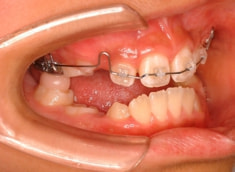

治療法:上顎拡大装置+フルパッシブブラケット(クリアスナップ)+フェイスマスク等

治療期間:12ヶ月

治療分析:日本人の反対咬合や下顎前突は、上顎の劣成長を伴なうことがほとんどで、本ケースも上顎劣成長でしたので、上顎を側方拡大と前方に牽引しました。側方拡大方法は急速拡大で正中口蓋縫合の拡大を行い、同時に横口蓋縫合を剥がす効果があり、前方牽引の効果を促進します。

治療前

治療後(12ヶ月後)